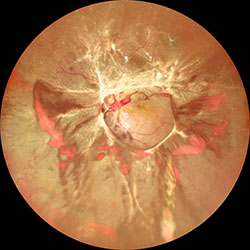

雖然玻璃體腔內注射抗血管內皮生長因子藥物后2周,

玻璃體出血減少,但在Mirante超廣角圖像上明顯可見累及黃斑的牽拉性視網膜脫離。

34歲男性糖尿病患者,主訴雙眼視力模糊2個多月。根據他的醫療記錄,右眼初始BCVA為20/100,左眼為20/125。雙眼前節無明顯異常。眼底成像顯示雙側增殖性糖尿病視網膜病變(PDR),視盤區域有增殖的纖維組織,左眼伴隨玻璃體出血(圖1)。此外,OCT顯示視網膜海綿樣腫脹,左右眼中央黃斑厚度分別為339μm和413μm。基于雙眼PDR合并黃斑水腫的診斷,由另一名醫生進行雙眼璃體腔內注射抗血管內皮生長因子藥物(Anti-VEGF)。然而,治療后2周,左眼視力從20/125下降到20/250,發現累及黃斑的牽拉性視網膜脫離(TRD)(見上圖)。因此,他被轉到我們門診接受進一步治療。

圖2. 經玻璃體切除術并行全視網膜光凝及硅油填充治療后,在Mirante超廣角圖像可見視網膜貼附良好。